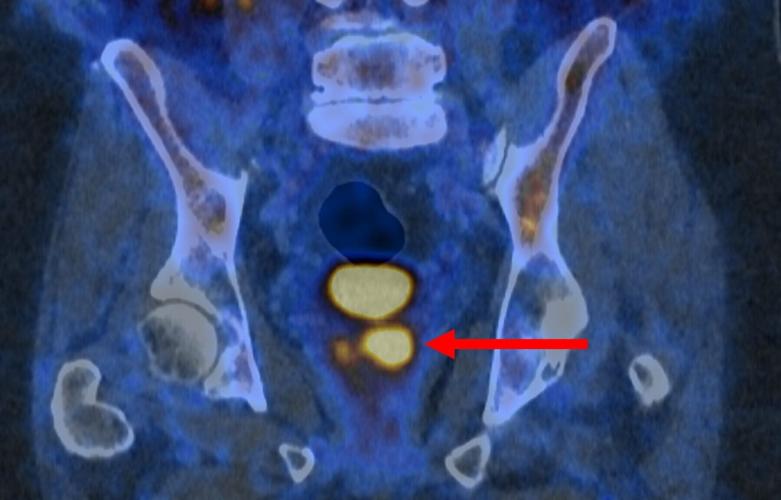

Glowing prostate cancer cells PSMA PET 2. (PRIMARY 2 via SWNS)

The PSMA PET/CT scan identifies more aggressive prostate cancer cells, which are potentially harmful and may need treatment.

It does so with a molecule that binds to prostate cancer cells and causes them to "light up in a remarkable way" - appearing as bright spots in the scanning image.

Dr. James Buteau, a nuclear medicine physician at the Peter MacCallum Cancer Centre, said: “PSMA PET/CT scanning makes prostate cancer cells light up in a remarkable way, particularly in more aggressive cancers.